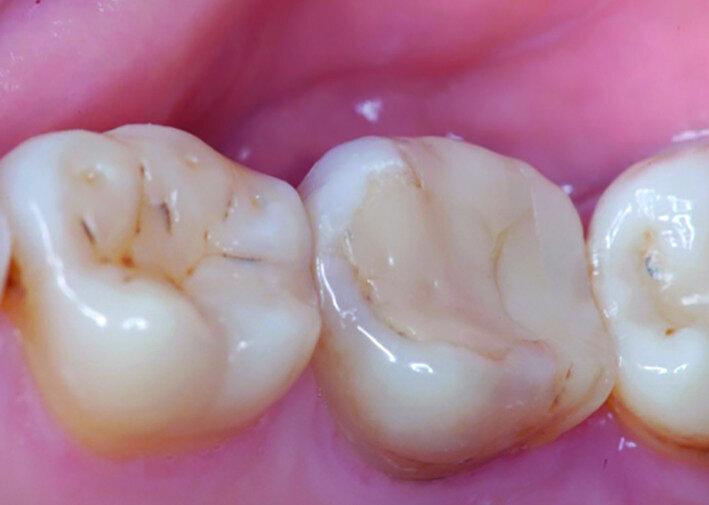

Fig. 14a: Clinical image: Pre-op.

The left mandibular second molar of a 35-year-old female patient had been compromised because of a vertical root fracture and a large periapical lesion was present. After explanation and informed consent, the treatment was scheduled. The right mandibular third molar was preferred as a donor to the left mandibular third molar because of a more compatible anatomy and for an easier stabilisation. After local anaesthesia of both the donor and the recipient sites with 2 per cent mepivacaine with 1:100,000 adrenaline, the left mandibular second molar was extracted and the alveolus debrided. Then the donor tooth was atraumatically extracted, quickly repositioned in the recipient site and stabilised with sutures at about 1.5–2.0 mm of infraocclusion. An antibiotic (amoxicillin/clavulanic acid, 1 g, by mouth twice a day for five days) and a non-steroidal anti-inflammatory drug (ibuprofen, 600 mg, by mouth twice a day for five days) were prescribed, along with rinses with 0.2 per cent chlorhexidine. The sutures were removed after two weeks and endodontic treatment was performed after three months. The periapical lesion healed and the tooth was fully functional after 12 years (Figs. 14a–d & 15a–d).